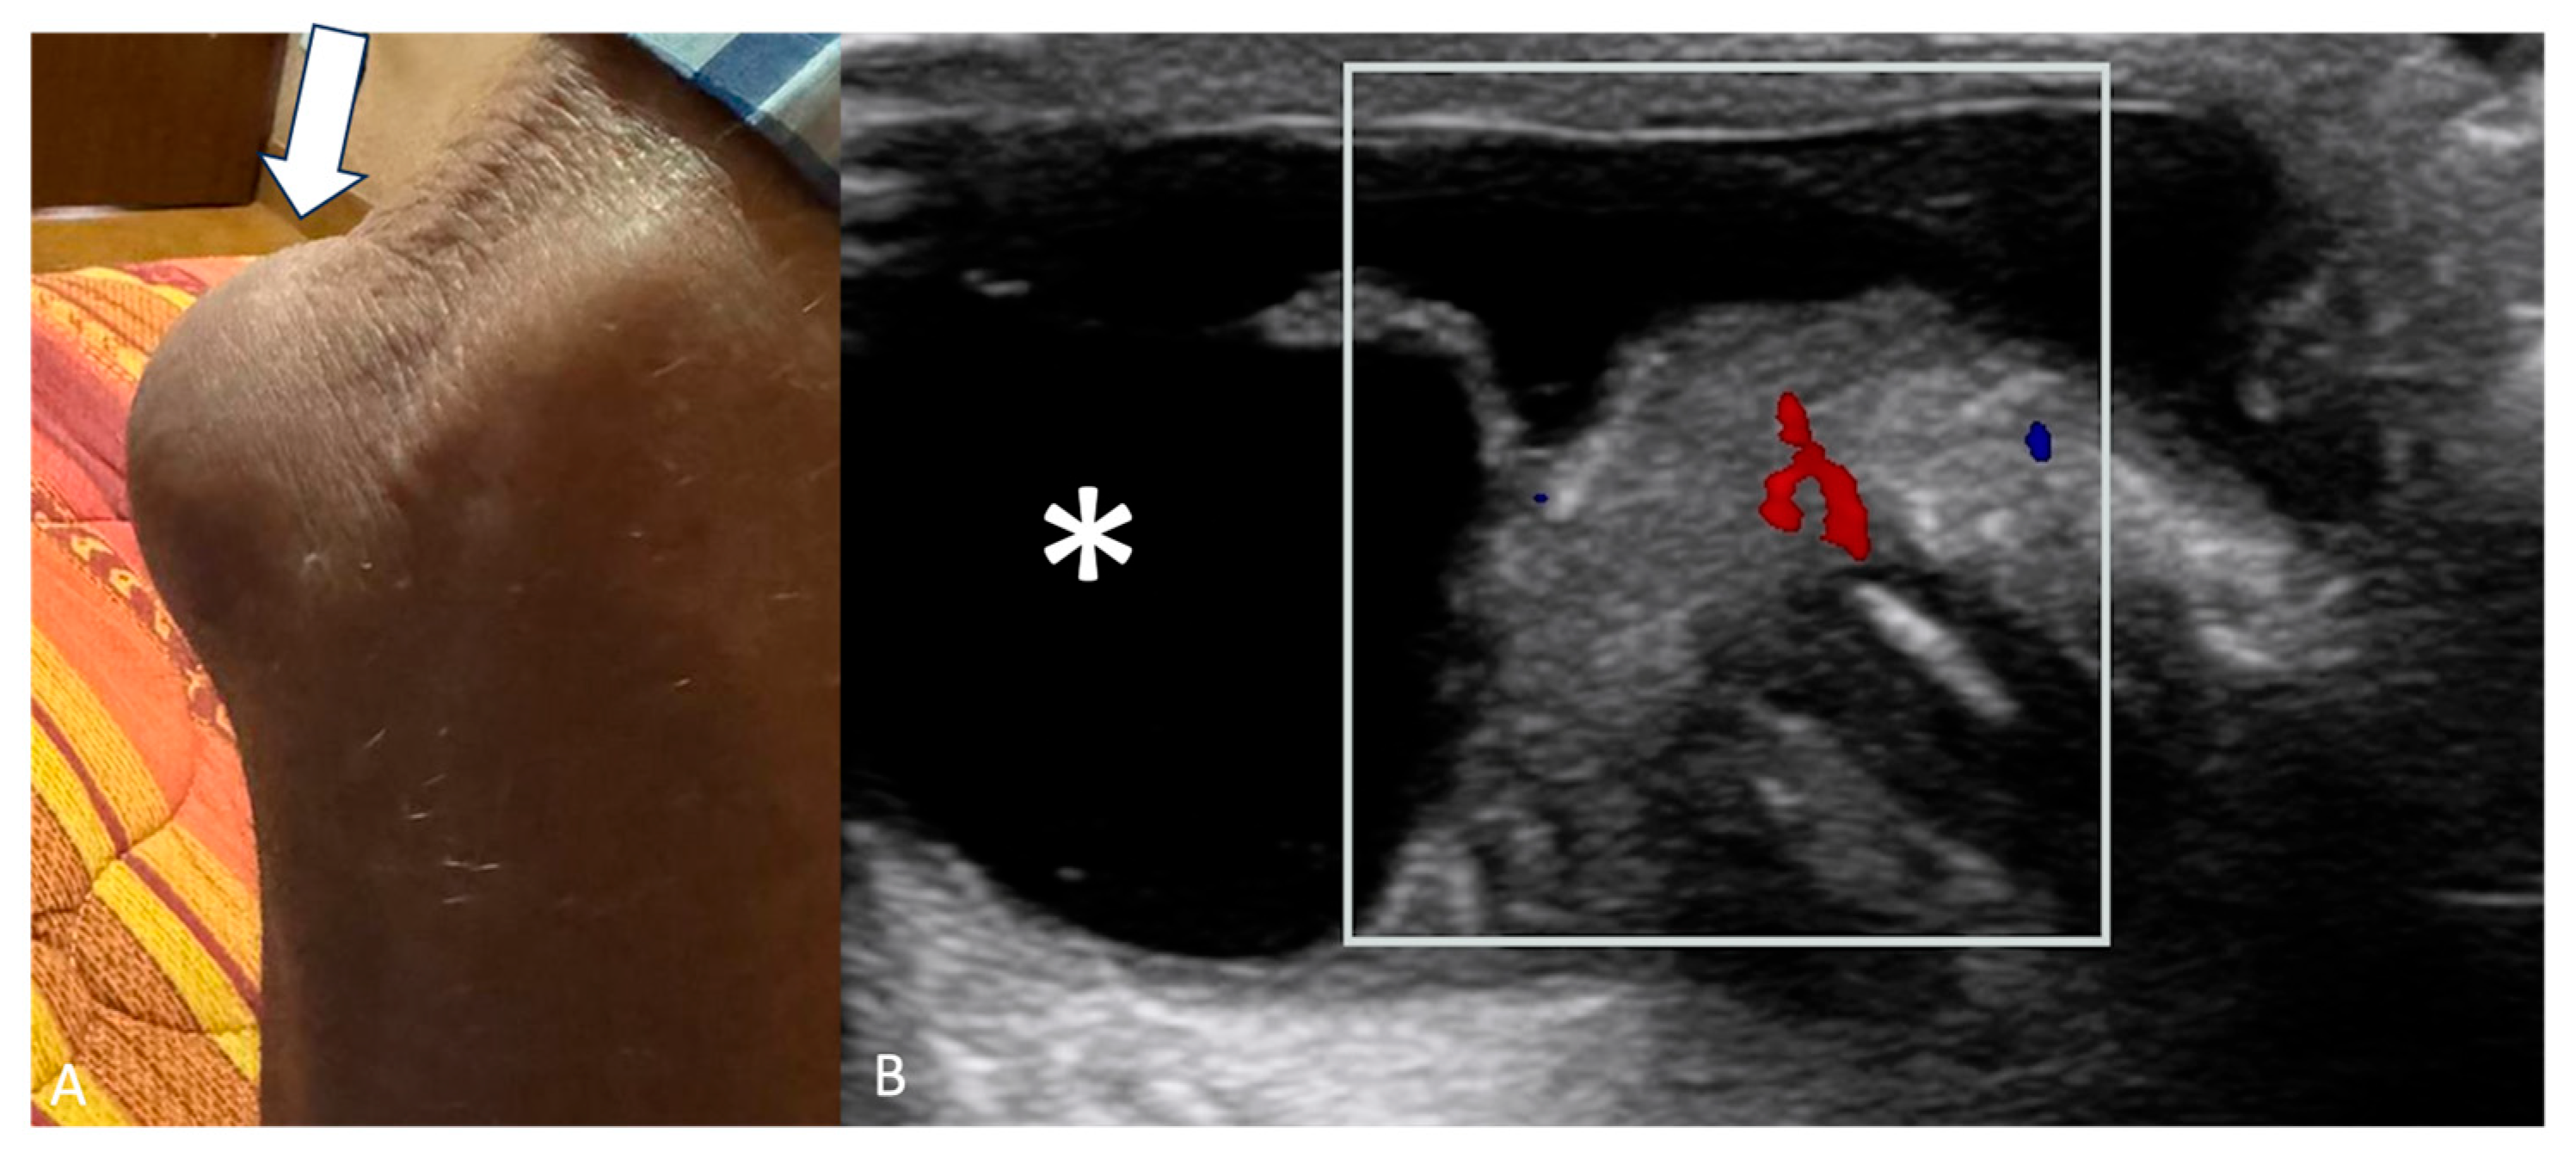

Bursitis may appear as a soft tissue mass around joints. Subacromial-subdeltoid (SASD) bursitis is the most common of the shoulder [12], olecranon bursitis (OB) (Figure 2) is the inflammation of the olecranon bursa, a fluid-filled sac overlying the olecranon process of the elbow [22], and trochanteric bursitis (TB) is a common cause of lateral hip pain due to inflammation of the trochanteric [23]. Increased vascularity on CD can aid in assessing active inflammation associated with bursitis but is not so common [17,18].

Figure 2.

(A) Right elbow of a 73-year-old male with a bump in the posterior region of the elbow (white arrow). (B) US shows anechoic fluid collection (asterisk) with thickened and hypervascular synovium (white box) overlying the olecranon process of the ulna, compatible with olecranon bursitis.